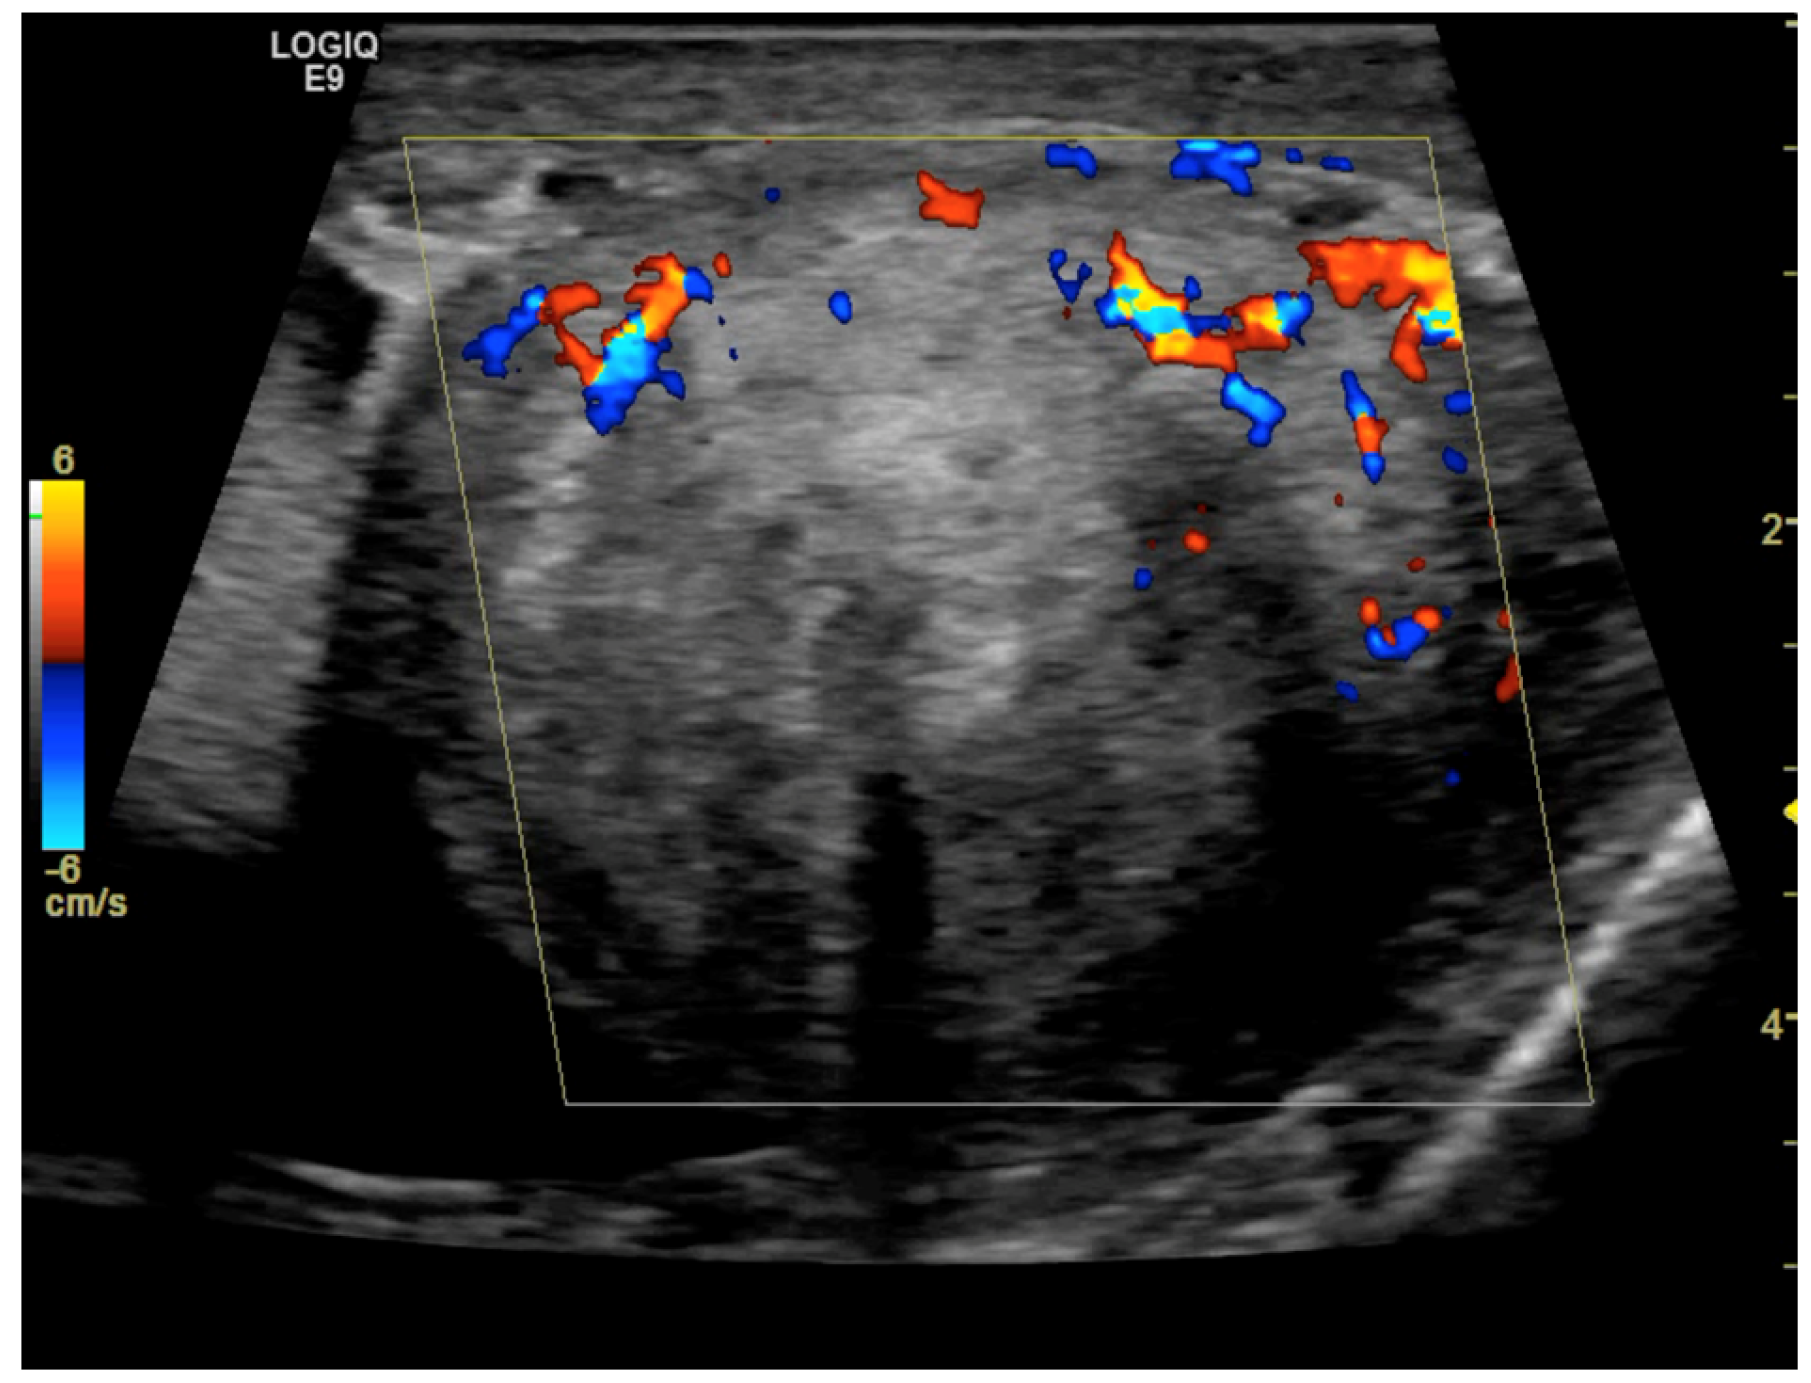

CD was employed to determine the vascularization of the mass. To maximize sensitivity to slow flow velocities, CD was performed using the highest signal gain setting possible (without the appearance of background noise) and low pulse repetition frequencies, allowing for the demonstration of peripheral lesional vascularity (Figure 3 and Video S2). A grade 4 varicocele was also diagnosed via Doppler sonography: dilatation of the veins of the pampiniform plexus around the testis to over 2.5–3 mm and backward flow toward the testes during Valsalva’s maneuver were observed (Figure 4).

Figure 3. Color Doppler image obtained using 8 MHz frequency transducer shows mainly peripheral Doppler signals within the mass.